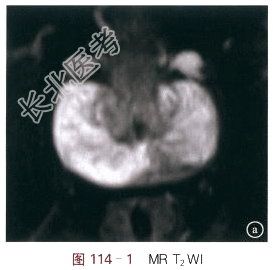

- [材料题] 男性,70岁,无不适,体格检查PSA升高。体格检查:直肠指检前列腺无明显包块,局部质硬。血检:PSA总(t)7.996,游离(f)0.694,f/t:0.087。影像学资料如图114-1~图114-4所示。

读片分析:图114-1MR-T₂WI脂肪抑制像示左侧外周带有一低信号结节,其边界不清,边缘不光整,信号不均匀,包膜完整,周围脂肪间隙清晰;图114-2DWI示病灶呈明显高信号灶,图114-3ADC示病灶呈明显低信号灶,ADC约为0.78×10-3mm2/s;图114-4T₁WI增强示病灶有早期强化。